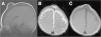

La resonancia magnética (RM) mostró la existencia de un proceso expansivo quístico (fig. 1), cuyo contenido mostraba una intensidad de señal similar a la del líquido cefalorraquídeo, situado en la fontanela anterior. Estaba recubierto por el cuero cabelludo, sin que existiera dehiscencia de la sutura. Tras la inyección de contraste paramagnético, la citada lesión no presentó captación del mismo (fig. 2).